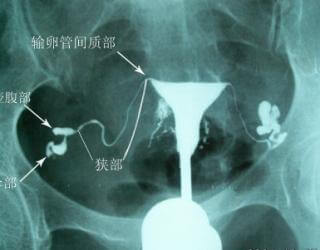

正常输卵管造影片子是什么样的?造影检查完之后,有一个片子,好多朋友看不太懂。下面,我们通过正常输卵管造影图,请不孕不育症专家,给大家分析下。

女性不孕专家指出:正常输卵管,细长又弯曲,输卵管的长度,一般在8-15公分左右,这个长度,因人而异。没有统计说,过长或过短的输卵管,就不能怀孕,输卵管的弯曲是正常的,炎症造成的弯曲是僵直的,是自己不打弯的,所以,我们不可凭空想向弯曲的就是病理现象。

输卵管造影怎么做?它通过X线,将管插入宫腔,推注定量造影剂,进行X拍片,可以观察到子宫腔大小形态、及堵塞的具体位置,对输卵管的形态,一目了然。影像延伸到输卵管的伞端口外,通过对X光的观察,可以看到造影剂,在患者的盆腔弥散。

当女性的输卵管堵塞时,会显示输卵管堵塞部位、程度以及堵塞的性质。这种方法还可辨认子宫内膜情况。是现在诊断输卵管通畅性比较的方法,在医疗过关的情况下,造影的率高达95%。

专家提醒:一般医院,对子宫输卵管造影的,要求比较高,插管的深度,造影剂推注的快慢,都会影响到最终的检测结果。因此,女性想要进行此类检查,较好是到正规医院进行,以免造成误诊。